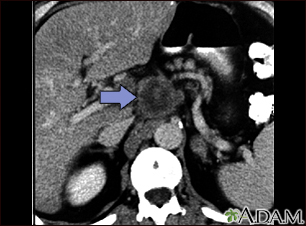

Pancreatic cancer, CT scanBackPancreatic cancer, CT scanA CT scan of the upper abdomen showing a tumor (pancreas carcinoma) in the head of the pancreas, seen here in the middle of the picture. E-mail FormEmail ResultsName:Email address:Recipients Name:Recipients address:Message: